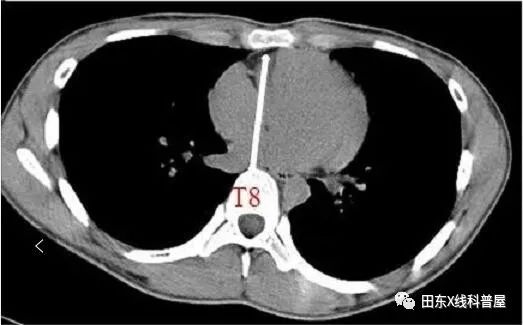

胸椎曲度弧高(左侧位胸片测量):T4-T12做一连线,测T8椎体前缘与该直线的垂直距离,其距离若<12mm,可考虑SBS。

测量胸廓前后径/横径比值≤0.33。

具体出来:胸椎曲度孤高<12mm,胸廓前后径/横径比值≤0.33。